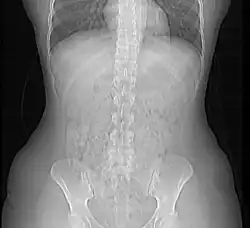

In de gezondheidszorg, met name binnen de radiologieafdeling van een ziekenhuis, wordt op grote schaal gebruikgemaakt van medische beeldvormende systemen (bijvoorbeeld röntgen, CT, MRI en echografie). De beelden worden aangemaakt door beeldvormende modaliteiten en uiteindelijk in beeldarchieven (PACS systemen) opgeslagen. De gegevensuitwisseling tussen deze systemen vindt plaats door middel van het uitwisselen van elektronische berichten. De structuur van die berichten wordt gedefinieerd door standaarden zoals DICOM. Naast DICOM wordt in de gezondheidszorg eveneens gebruikgemaakt van onder andere de HL7- en EDIFACT-EDI-standaarden.